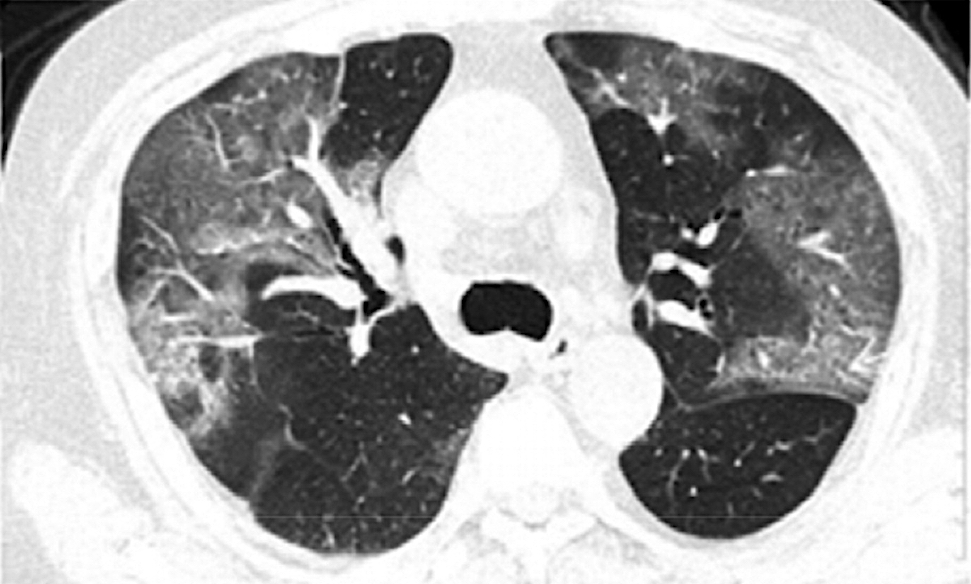

Cependant, dans le contexte de l’épidémie chinoise, cette

approche plus pragmatique s’avère mieux adaptée, d’autant que, dans

une série de 41 cas publiée dans Radiology (1), la signature

radiologique de l’infection est constante. Les opacités pulmonaires

sont bilatérales et évocatrices par leur association à d’autres

stigmates (destruction parenchymateuse, inflammation interstitielle

et consolidation extensive) comme le rappelle une publication

chinoise en ligne encore plus récente dans le même journal (2),

laquelle décrit l’évolution des signes radiographiques et

tomodensitométriques dans les jours qui suivent l’admission. La

série compte 21 patients (âge 25-63 ans, hommes : n=6) atteints de

COVID-19 et hospitalisés entre le 12 janvier 2020 et le 6 février

2020.

(1) stade 1 (0-4 jours) : opacités en verre dépoli dans trois

quarts des cas (18/21), score TDM total 2 ± 2;

(2) Stade 2 (5-8 jours): majoration ou apparition d’un aspect

dit en « pavage irrégulier » correspondant à la

superposition de septa interlobulaires ou interstitiels épaissis et

d’opacités en verre dépoli dans 53 % des cas (9/17) (score TDM

total en augmentation significative 6 ± 4, p=0,002);

(3) Stade 3 (9-13 jours): consolidation dans 91 % des

observations (19/21) le score TDM total atteignant son pic (7 ±

4)

(4) stade 4 (≥ 14 jours): disparition progressive des signes

de consolidation dans les trois quarts des cas (15/20), le score

TDM moyen étant alors de 6 ± 4 et l’aspect de pavage irrégulier

disparaissant complètement.